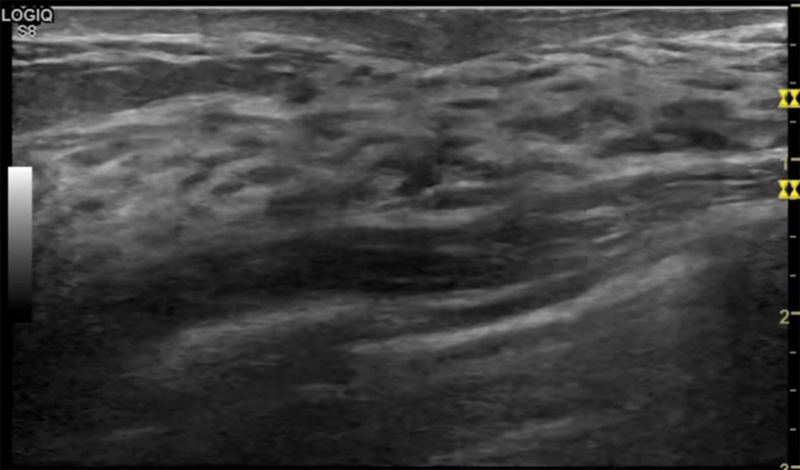

乳房脹痛,觸摸疼痛,手摸起來感覺有腫塊。這個是什麽問題呢?醫生診斷一般是乳腺增生。那麽在乳腺秋葵视频APP下载安装檢查後,報告單卻顯示雙乳未見明顯占位性病變。乳腺增生是很多女性,特別是育齡期女性都有的經曆、到底乳腺增生症狀有哪些?會給秋葵视频男人的加油站帶來怎樣的影響呢?乳腺增生不是腫瘤跟炎症。乳腺組織增生及退行性變跟內分泌功能紊亂有關係。正常的生理改變。還有乳腺病,良性乳腺結構不良等名稱。

乳腺增生有什麽症狀,病因?比較典型的就是乳房疼痛,特別是經前症狀比較重,經後就有所緩解。有時候還能碰到乳房硬塊。根據經期的變化而變化硬度大小都有變。乳腺在內分泌激素,伴隨月經周期有增生問題。內分泌激素代謝失衡,雌激素水平增高,出現乳腺組織增生過度,增生組織不退的情況下,就會有乳腺增生症狀。這個不會增加乳腺癌的風險。所以不用緊張的。不過乳腺癌的病人都會有乳腺增生。所以乳腺增長有沒症狀,都需要進行常規的體檢。